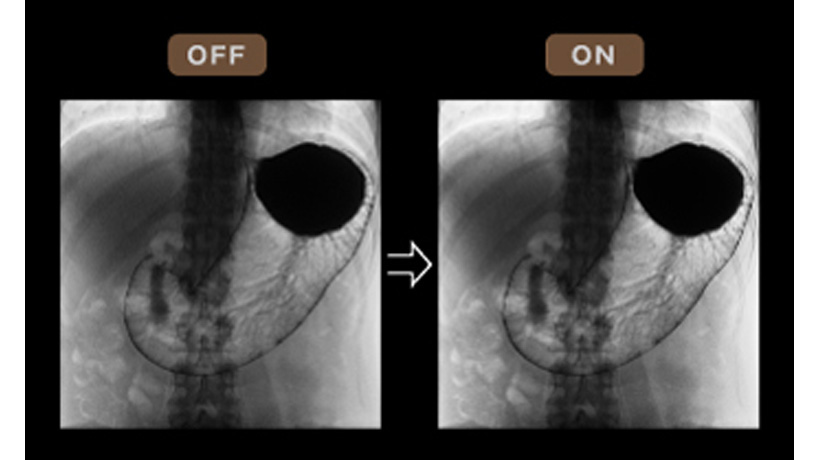

Retinex理論に基づき、透視画像の局所ごとにコントラスト補正を行うことにより、低コントラスト帯の視認性を向上する技術です。 椎体・ハレーション部における、胃との重なり部分の視認性が向上します。M-DRCと処理と組み合わせることで、より効果的です。